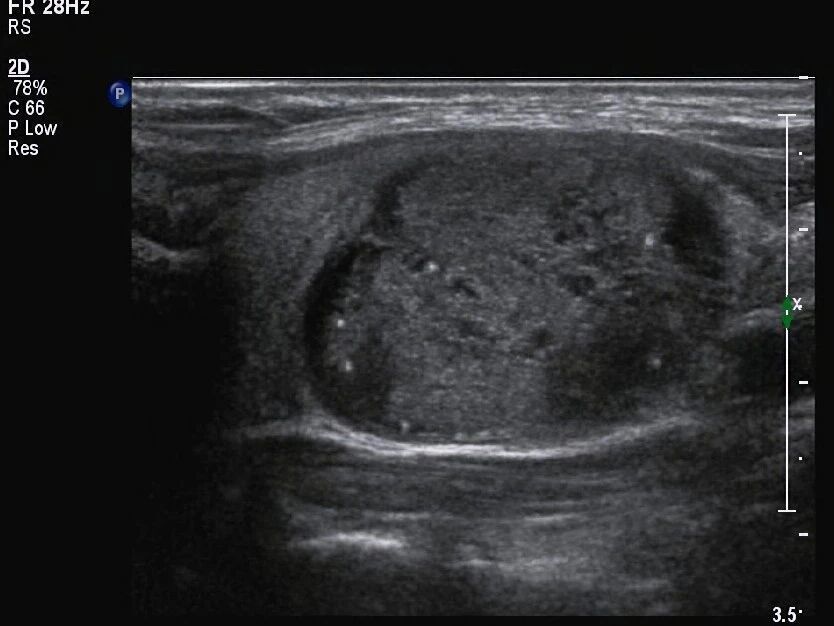

在甲状腺超声里,有好些小于1毫米的亮点,这些亮点有隐藏重要信息的可能,这些叫做点状强回声,有时这些点状强回声后方带着呈逐渐减弱态势的平行线条,样子类似彗星尾巴,这种情况通常是浓缩胶质形成的混响伪像,然而实际诊断时,医生常碰到既无声影又无可观察彗尾征的强回声点,这时判断其性质就特别困难了。

点状强回声出现,其后方伴有声影,这属于典型的微钙化表现,多条平行强回声存在,向深部延伸,这是由浓缩胶质形成的彗星尾伪像,然而在临床实践当中,这两种特征并非总是如此典型,小于1毫米的微钙化,可能不会产生明显声影,给准确判断造成了难度 。

囊实性结节,存在包含液态的囊性部分,还存有含有固态的实性部分,这种具备混合结构的状况,给诊断带来特殊挑战,要留意的关键在于,其与由大量微小囊腔构成、基本没有实性成分的海绵状结节有着本质差别 。